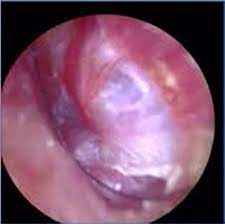

10 Causes Of Ear Fullness Arches Tinnitus Formula Natural Treatment For Tinnitus from www.tinnitusformula.com Now getting dizzy during a water irrigation is common. The ear wax may be the root. You'll get so much help and advice about pulsatile tinnitus. Pulsatile tinnitus is a ringing in one ear that follows a rhythm. Doctors rarely know about the difference between the two and treat them similarly. There should be an examination of the ears with an otoscope. The ringing or buzzing you hear with other kinds of tinnitus is a result of nerves picking up on abnormal electrical signals moving from your ears to your brain. Not really a sign of anything.

Pulsatile tinnitis can be a sign of a conductive hearing loss.

Wax should be removed, and the examiner should note whether the ear drum. Now the left ear is starting to clog up!! Without drugs, without risky surgery, without any typical tinnitus treatments, and. Pulsatile tinnitus (pt) is a symptom that affects nearly five million americans. Find out what causes it and how to treat it. People may also hear whooshing, grinding, hissing or whistling noises. Pulsatile (or vascular) tinnitus is a form of tinnitus and is usually heard in sync with the persons pulse. I've been puttin ear drops and olive oil in my ears hopefully that has soften the wax up. Pulsatile tinnitus, sound therapy. american hearing research foundation: Pulsatile tinnitus is a ringing in one ear that follows a rhythm. Symptoms of pulsatile tinnitus pulsatile tinnitus causes pulsatile tinnitus diagnosis pulsatile tinnitus treatment faqs. Pulsatile tinnitus is a rarer form. Fast forward a month and i mention the earwax blockage/tinnitus in passing to my gp, so she looks inside my ears and says it's all clear, great;

I would say the tinnitus was about 7.5/10. It can be described as similar to that of the rhythm of a heart rate. There should be an examination of the ears with an otoscope. Read more about its causes and treatment here. Wax should be removed, and the examiner should note whether the ear drum. Like regular tinnitus, the pulsatile form of this condition has ringing in the ear as its chief symptom. I've been puttin ear drops and olive oil in my ears hopefully that has soften the wax up. Hearing heartbeat, fluttering, whooshing sound in ear. Pulsatile tinnitus, sound therapy. american hearing research foundation: Fast forward a month and i mention the earwax blockage/tinnitus in passing to my gp, so she looks inside my ears and says it's all clear, great; Not really a sign of anything. Pulsatile tinnitus (pt) is a symptom that affects nearly five million americans. They may experience it while lying down or sleeping on one side or during pregnancy.